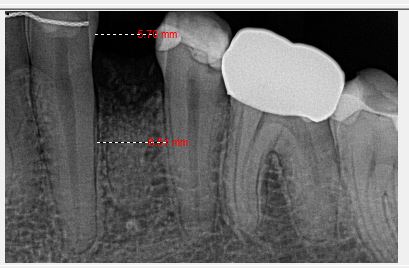

I recently placed an implant that I’m worried about the prognosis. My previous cases have all been free handed. I had my lab make a guide for this case. I ended up relying too much on the guide and placed the implant too close to the adjacent tooth (0.8mm). Has anyone else placed one this close and had it fail or be successfull? Im…

Anecdotally, I have at times, and many others have placed implants closer than we wish we would have to adjacent teeth. It’s happened once or twice. And aside for a few sleepless nights, I (and the patient) have had zero issues from it.<br…

In my humble opinion, the first thing is to take a step back and not stress too much. Thing will be okay.

Option A: Take the implant out and re-do the implant placement. You still have time if you wan to do this.

Yes, it does feel stressful to explain to the patient why you want… Read more